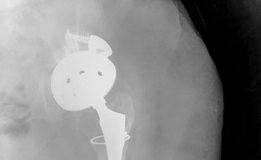

1. Cup Cage Constructs: A highly porous hemispherical cup is impacted into the defect and fixed with screws. An ilioischial cage is then contoured and placed over the cup, spanning the discontinuity. The cage is secured to the ilium proximally and the ischium distally. A polyethylene liner is then cemented into the cage. This technique relies on the cage for immediate mechanical stability while allowing the underlying porous cup to achieve biological ingrowth.

2. Custom Triflange Acetabular Components (CTAC): For the most severe, uncontained defects where modular augments or cages are insufficient, a CTAC is designed based on the patient's preoperative CT scan. The implant features flanges that extend onto the ilium, ischium, and pubis, allowing for screw fixation into optimal host bone corridors. While highly effective, CTACs require significant lead time for manufacturing and are expensive.

In the presence of Paprosky IIIB defects or pelvic discontinuity (a complete separation of the superior and inferior hemipelvis), the reconstructive complexity escalates significantly. The goal is to bridge the discontinuity and achieve stable fixation in both the ilium and the ischium/pubis.